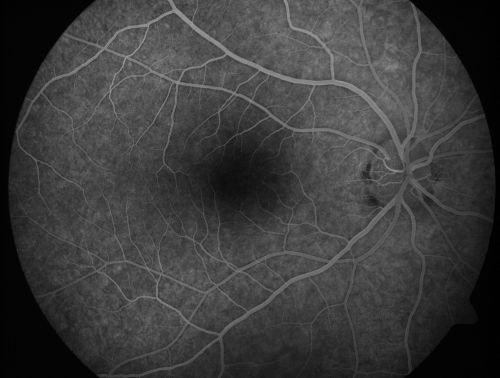

Toxoplasmosis Macular Scar (acquired not congenital) 31 Year Old Man- Recent Vision Change - Creeping Scar

31-year-old man had an episode of toxoplasmosis in the left eye, where unfortunately it adversely affected his central vision that was back in 2004 (7 years ago)

He did notice recently a change in his visual function.  He plays softball, he was getting hit by the ball and having trouble seeing and he said that is how he noticed the toxoplasmosis when it first occurred and he was concerned it might have recurred.

OD 20/16,  OS 20/80.